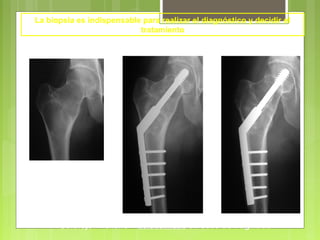

La biopsia es indispensable para realizar el diagnóstico y decidir el

tratamiento

Cirugía

- Amputación

- Resección y reconstrucción

(por medio de prótesis)

Osteosarcoma

Tumores malignos: cirugía de exéresis y de

reconstrucción

Osteosarcoma Mujer de 25 años

La resección se debe realizar a distancia de la lesión

Prótesis de reconstrucción